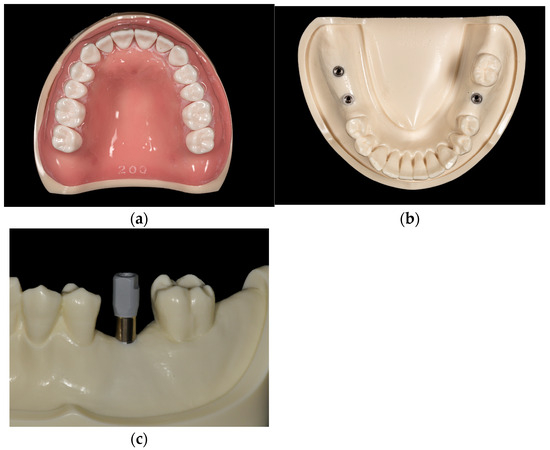

CBCT Assessment for Dental Implant Surgery at the Maxilla: A Clinical Update

In contemporary practice, dental implants are widely recognized as a reliable and effective solution for rehabilitating edentulous patients. Nevertheless, implant placement in the atrophied maxilla presents considerable challenges, with treatment planning influenced by various factors such as patient demographics, anatomical constraints, and economic [...] Read more.

In contemporary practice, dental implants are widely recognized as a reliable and effective solution for rehabilitating edentulous patients. Nevertheless, implant placement in the atrophied maxilla presents considerable challenges, with treatment planning influenced by various factors such as patient demographics, anatomical constraints, and economic considerations. Advances in imaging technology have positioned cone-beam computed tomography (CBCT) as the preferred modality for enhancing implant placement accuracy. By producing high-resolution three-dimensional radiographic images, CBCT facilitates precise assessment of maxillary anatomy at the proposed implant site—including bone height, width, length, and angulation—thereby optimizing surgical planning and improving the predictability and success rates of implant integration. Moreover, the timing of implant placement must account for the necessity of maxillary augmentation to ensure implant stability and reduce the risk of postoperative complications. This review discusses the clinical utility of CBCT as a diagnostic tool for preoperative assessment, focusing on the identification of critical anatomical landmarks and the determination of indications for bone augmentation, thereby highlighting its crucial role in enabling accurate treatment planning, minimizing surgical risks, and promoting the long-term survival of dental implants. Full article

Show Figures

Figure 1